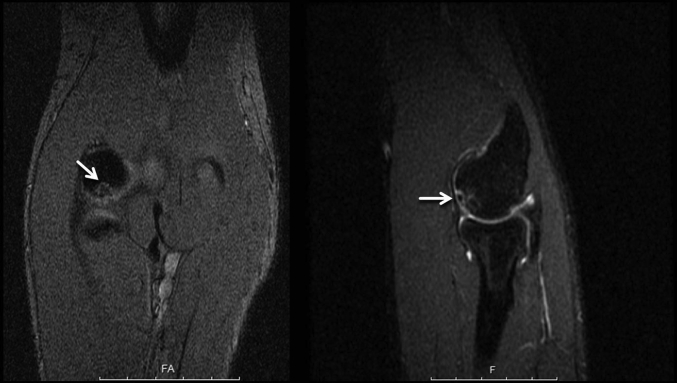

Fig 1.

Coronal and sagittal magnetic resonance imaging of an osteochondritis dissecans lesion of the capitellum (arrows) in a right elbow. In this instance, high signal intensity behind the osteochondritis dissecans lesion is suggestive of partial or complete delamination of the fragment. It is critical that stability of the fragment is assessed at the time of surgery.